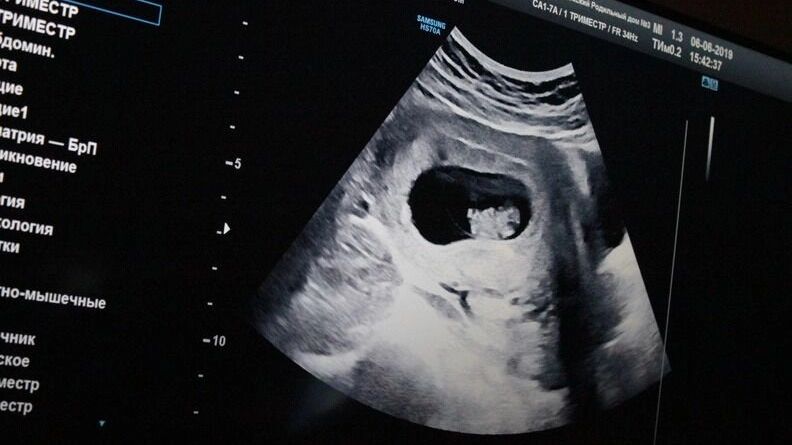

В России началась новая волна борьбы за рождаемость — теперь она официально стала показателем эффективности региональных властей. Одни субъекты федерации заманивают будущих матерей денежными бонусами, другие — открыто давят на отказ от аборта. Но именно Нижегородская область в этой гонке выделилась особенно громко: здесь решили создать так называемый «демографический спецназ».

В регионе появится сеть специальных служб, задача которых — «работать» с женщинами, решившими прервать беременность. Подразумевается, что это будет происходить при участии психологов, социальных работников, медиков, а возможно — и представителей духовенства. Цель — убедить женщину не делать аборт.

«Основная суть — помочь женщине отказаться от аборта еще на начальном этапе принятия этого тяжелейшего решения. Задача — выявлять первые запросы, когда женщина начинает сомневаться и искать информацию в интернете, и дальше уже предлагать ей консультационную поддержку, направленную на сохранение зарождающейся жизни», — пишет губернатор Глеб Никитин.